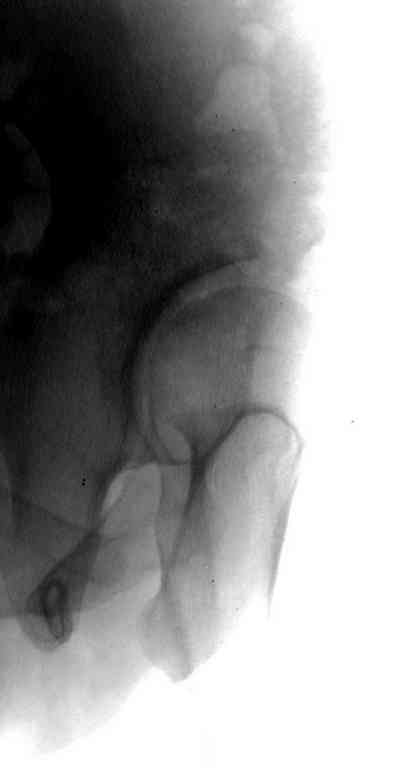

Имя     : Displasia False profile.jpg

Тип     : image/jpeg

Размер  : 11567 байтов

Описание: отсутствует

Url     : http://weborto.net:8080/pipermail/ortho/attachments/20101217/2fe082a4/attachment-0003.jpg

Данный сустав в начальной стадии разрушения, но все-таки я бы сделал обзорный таз и отдельные снимки сустава в 30 градусной абдукции и аддукции. Также снимки с внутренней и наружной ротацией для оценки состояния головки бедра.